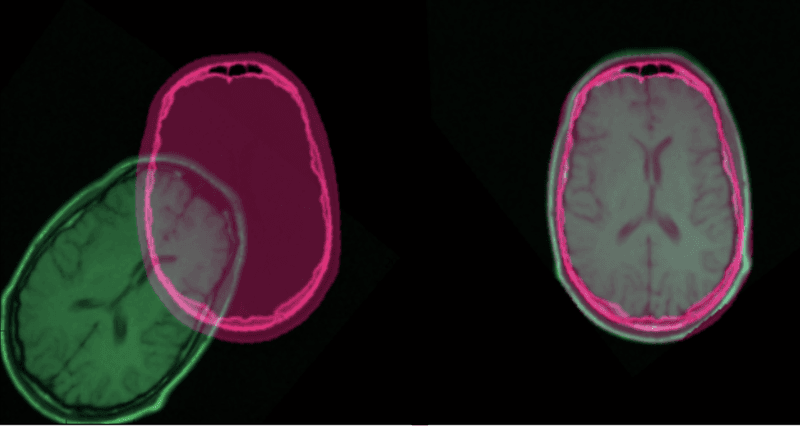

Image registration is the process of transforming different images of one scene into the same coordinate system. These images can be taken at different times (multi-temporal registration), by different sensors (multi-modal registration), and/or from different viewpoints. The spatial relationships between these images can be rigid (translations and rotations), affine (shears for example), homographies, or complex large deformations models.

Image registration has a wide variety of applications: it is essential as soon as the task at hand requires comparing multiple images of the same scene. It is very common in the field of medical imagery, as well as for satellite image analysis and optical flow.

Since the early 2000s, image registration has mostly used traditional feature-based approaches. These approaches are based on three steps: Keypoint Detection and Feature Description, Feature Matching, and Image Warping. In brief, we select points of interest in both images, associate each point of interest in the reference image to its equivalent in the sensed image and transform the sensed image so that both images are aligned.

After matching at least four pairs of keypoints, we can transform one image relatively to the other one. This is called image warping. Any two images of the same planar surface in space are related by a homography. Homographies are geometric transformations that have 8 free parameters and are represented by a 3x3 matrix. They represent any distortion made to an image as a whole (as opposed to local deformations). Therefore, to obtain the transformed sensed image, we compute the homography matrix and apply it to the sensed image.

Complex Transformations

A significant proportion of current research in image registration concerns the field of medical imagery. Often times, the transformation between two medical images cannot simply be described by a homography matrix because of the local deformations of the subject (due to breathing, anatomical changes, etc.). More complex transformations models are necessary, such as diffeomorphisms that can be represented by displacement vector fields.

- In 2017 De Vos et al. proposed the DIRNet. It is a network that used a CNN to predict a grid of control points that are used to generate the displacement vector field to warp the sensed image according to the reference image.